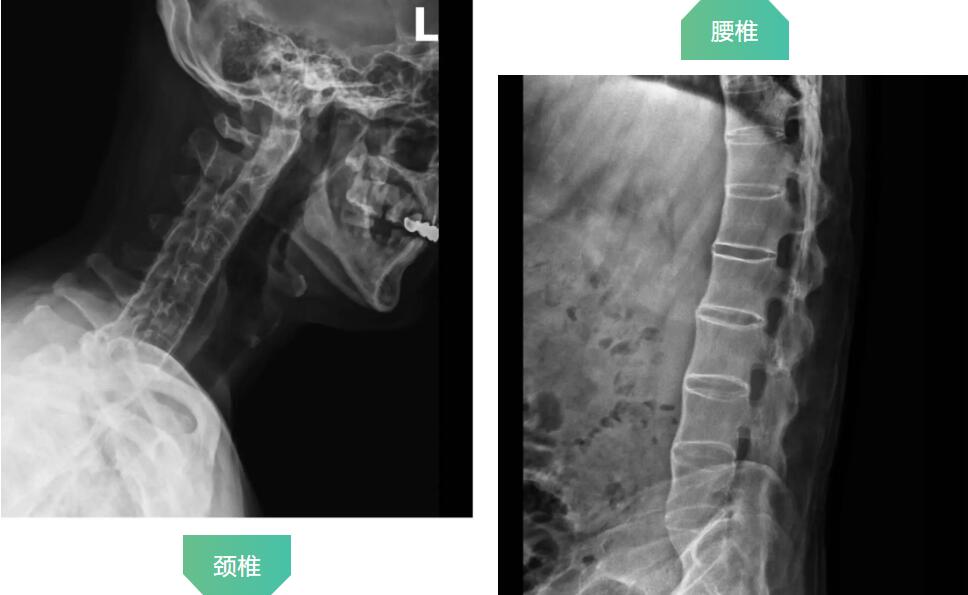

拍片顯示患者頸椎和腰椎已經(jīng)完全融合

羅軍主任分析患者病情,認(rèn)為他強(qiáng)直性脊柱炎30年,雙髖關(guān)節(jié)強(qiáng)直,骨贅增生嚴(yán)重,嚴(yán)重影響行走功能,診斷為強(qiáng)直性脊柱炎,雙側(cè)髖關(guān)節(jié)骨關(guān)節(jié)炎晚期。治療方案只有人工髖關(guān)節(jié)置換這一種選擇。因患者的頸腰椎已經(jīng)完全融合,手術(shù)和麻醉都是一個(gè)不小的挑戰(zhàn),羅軍主任帶領(lǐng)關(guān)節(jié)置換團(tuán)隊(duì)協(xié)同麻醉科團(tuán)隊(duì),經(jīng)過嚴(yán)密細(xì)致的討論,與患者及家屬充分溝通交流后,決定行機(jī)器人輔助DAA入路全髖關(guān)節(jié)置換術(shù)。機(jī)器人輔助加微創(chuàng)置換,為這項(xiàng)高難度手術(shù)提供了有力支撐。